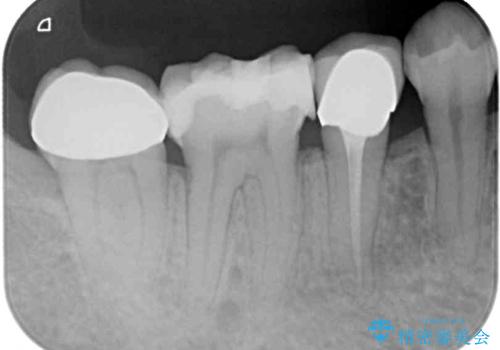

ドイツやベルギーなどで治療を受けた奥歯2本が食事の度にしみているとのことで、レントゲン検査や視診を行ったところ、補綴物や修復物の適合が悪く、それが原因であると考えられました。

いずれの歯も症状に異常なく、オールセラミッククラウンにて補綴治療を行うこととしました。